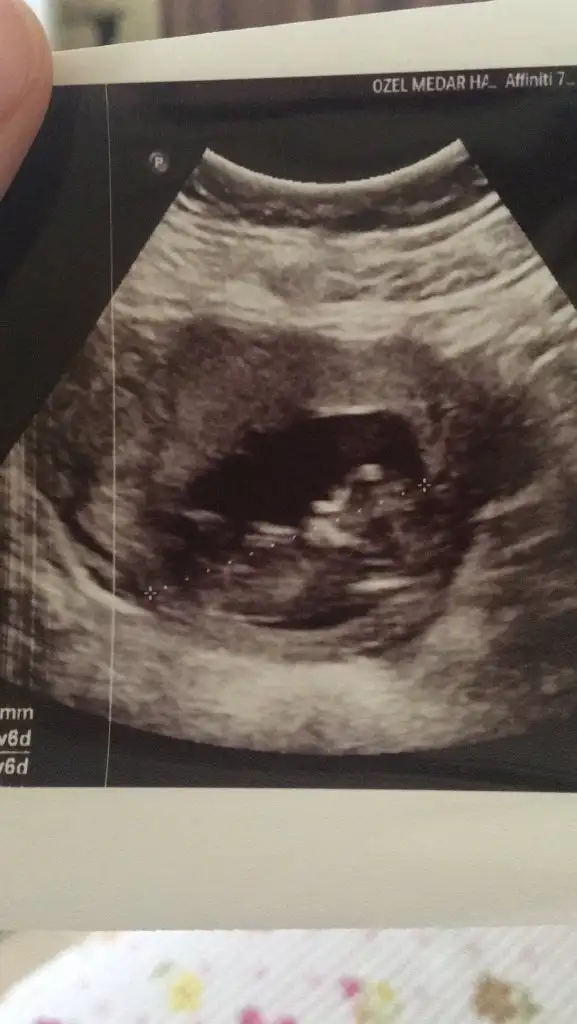

Merhaba yeni uyeyim elimde 7 haftalik karindan 10 haftalik alltan ulturason goruntusu var cinsiyet tahmini yapabilirmisiniz acaba şimdiden teşekkurler ilk resim 7 hafta karin son resim 10 haftta altan bakildi.

İlk iki foto alttan bakılandan son foto normal daha öncede atmıstım ama cok belli değil demiştiniz bu şekilde bi tahmin olabilirmi Ikra meyra Ikra meyra ☺️